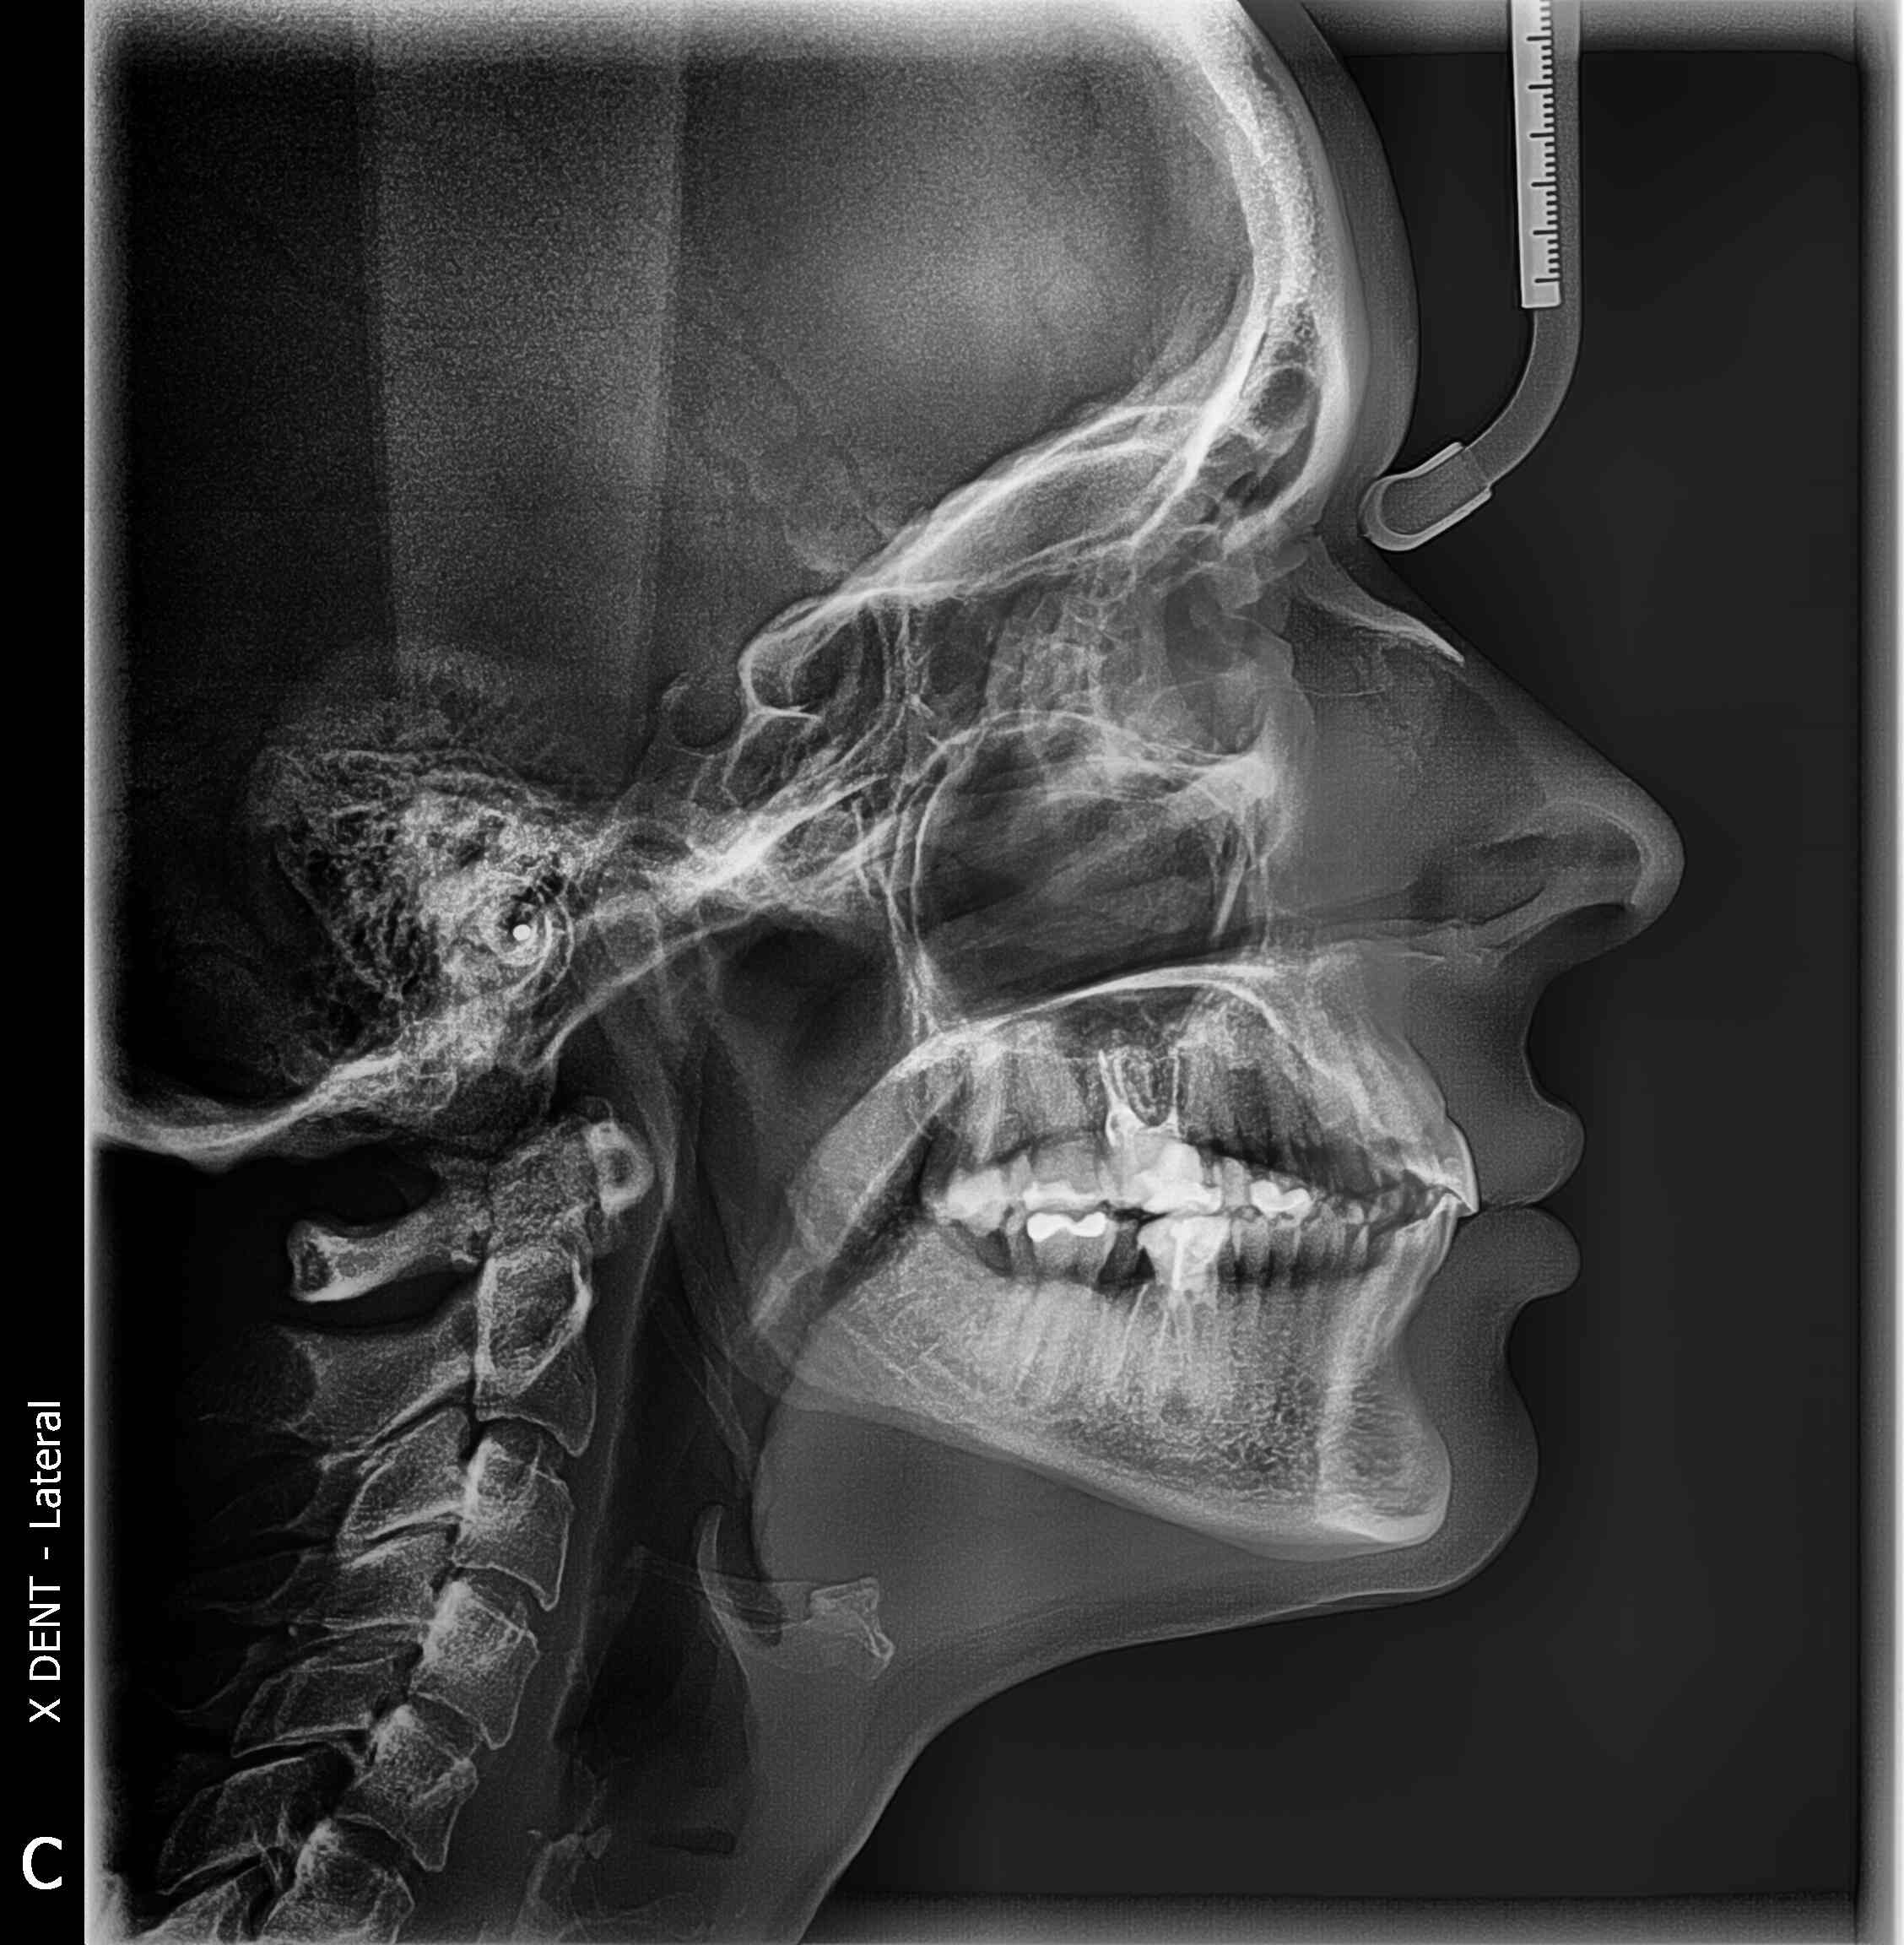

Telerendgen (tele RTG) je specijalna vrsta rendgenskog snimanja glave i vilice koja omogućava detaljnu analizu odnosa između vilica, zuba i lobanje. Ovaj snimak se često koristi u ortodonciji i oralnoj hirurgiji, jer pruža ključne informacije o strukturi i položaju kostiju lica, što je neophodno za planiranje terapija kao što su fiksne proteze, hirurške korekcije i implantati.

Telerendgensko snimanje koristi minimalne doze rendgenskog zračenja kako bi proizvelo jasne slike bočnog (latero-lateralnog) ili prednjeg (postero-anteriornog) pogleda na lobanju i vilice. Digitalni telerendgen omogućava brzu obradu i analizu snimka, što znači da stomatolog ili ortodont može odmah pristupiti podacima i kreirati precizan plan terapije.

Telerendgen snimak